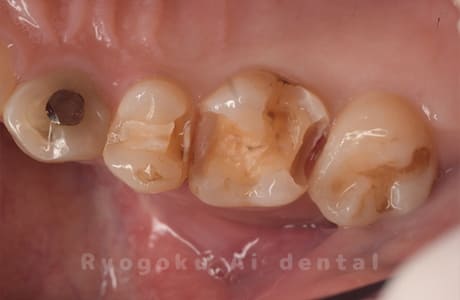

Case10

-

- 原因

- インレー2次カリエス、コンタクトカリエス

- 治療内容

- セラミックインレー、ダイレクトボンディング

- 治療費用

- 77,000円+66,000円

銀歯の部分が噛むと違和感があるとのことで来院されました。右上4番5番の歯の治療をセラミックインレーとダイレクトボンディングで治療した症例です。

<リスク・副作用>

過度の咬合や衝撃で割れることがあります。